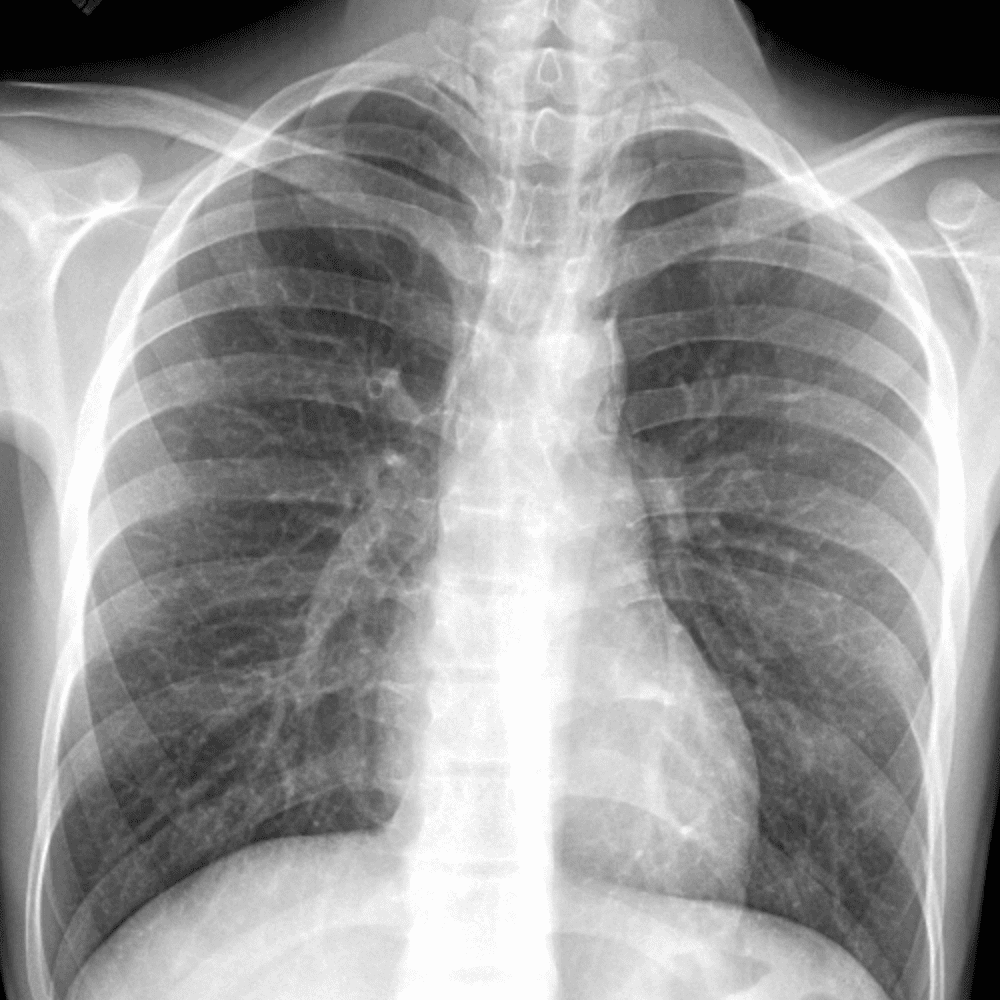

Peds Chest

Practice

Simulates call by including subtle or difficult cases and some normals.

50 cases